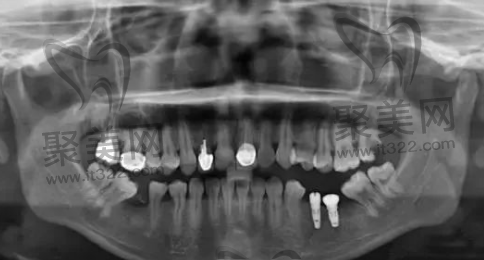

美国3i种植体所用的技术是在传统种植牙的基础上,用特殊的手术方式和技术将创伤尽量降低到较小,使整个治疗过程中不会有太大的压力。

效果展示

美国3i种植体怎么样 美国3i种植体 美国3i种植体价格